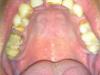

wind Опубликовано 22 апреля, 2010 Поделиться Опубликовано 22 апреля, 2010 (изменено) Добрый день мне 38 лет и захотелось навести порядок во рту те1 Поставить импланты на место отсутствуюших 4-к( отсутствует с 28 лет)2 раздвинуть зубы3 поставить имплант на место резца (отсутствует с 12 лет)Там где я живу не сильно большой выбор кому "отдаться" и самое главное поговорив с несколькими ортодонтами , меня зачаровало различие в подходах и оценки ситуации:1 оценки срока на раздвижение зубов розняться от 1,5 года до 3лет- ну это ладно , понять можно2 было мнение ,что есть небольшой шанс( но все же есть), когда они просто не раздвинутся , останутся на месте и все - возможно ли такое?3 кто говорит, что брекеты достаточно будет поставить только на верхнюю челюсть, а кто ,что на обе - и это обязательно- кто из них прав?( разумная экономия средств приветствуется)4 кто говорит, что импланты на 4-и нужно ставить после того как процесс раздвижения зубов закончится по тому что в противном случае: 1.1 импланты вылетят -1я версия 1.2 не дадут раздвинуться зубам-2я версияа кто говорит ставь ничего страшного, не помешает, и проблем не будет -3я версия5 и последнее - кто то говорит, лучше ничего не двигай вообще- типа опасно ,сложнореализуемо и тп.помогите разобраться пожалуйста Всем заранее благодарен....PS хочу добавить,1 перфекционизмом не страдаю , поэтому готов обойтись улыбкой по проще чем у звезды голивуда, меня устроит отсутствие щели спереди 2 не хотелось бы попасть в грусную ситуацию о которой пишут некоторые здесь люди(про некачественные услуги и потерянное зря время) Изменено 22 апреля, 2010 пользователем wind Ссылка на комментарий

Премоляр Опубликовано 22 апреля, 2010 Поделиться Опубликовано 22 апреля, 2010 Судя по вашей инфе,можно предложить-1-брекет система на 2 челюсти2-удаление корня 5ки сверху справа3-закрытие промежутка слева сверху дистализацией 4.3.24-импланты в обл резца и 4 слева...наверно есть еще варианты Ссылка на комментарий